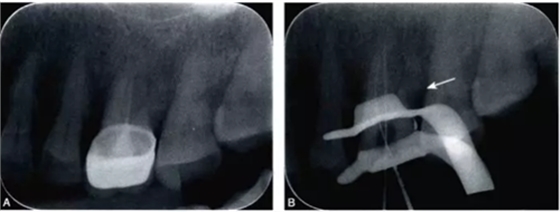

患牙常規(guī)開髓、暴露髓腔后發(fā)現(xiàn)小號(如10號及以下)根管銼進入根管困難,或無法探

查到根管,提示有細小鈣化根管存在的可能。除了通過根管探針或根管銼探查外,一般還需要結(jié)合以下多種手段進一步輔助檢查,才能夠得到較為準(zhǔn)確的診斷。

完全鈣化根管在X線片上的表現(xiàn)是根管影像模糊,密度增高,根管密度與周圍的牙本質(zhì)密度接近,甚至無法區(qū)分根管與牙本質(zhì)的影像。有些根管,可表現(xiàn)為根管影像時斷時續(xù)或模糊不清,為不完全鈣化根管表現(xiàn)(圖4-1A)。細小根管的病例在X線片上,根管影像隱約可見,與同名牙或鄰牙相比,根管較為細小影像清晰度降低。